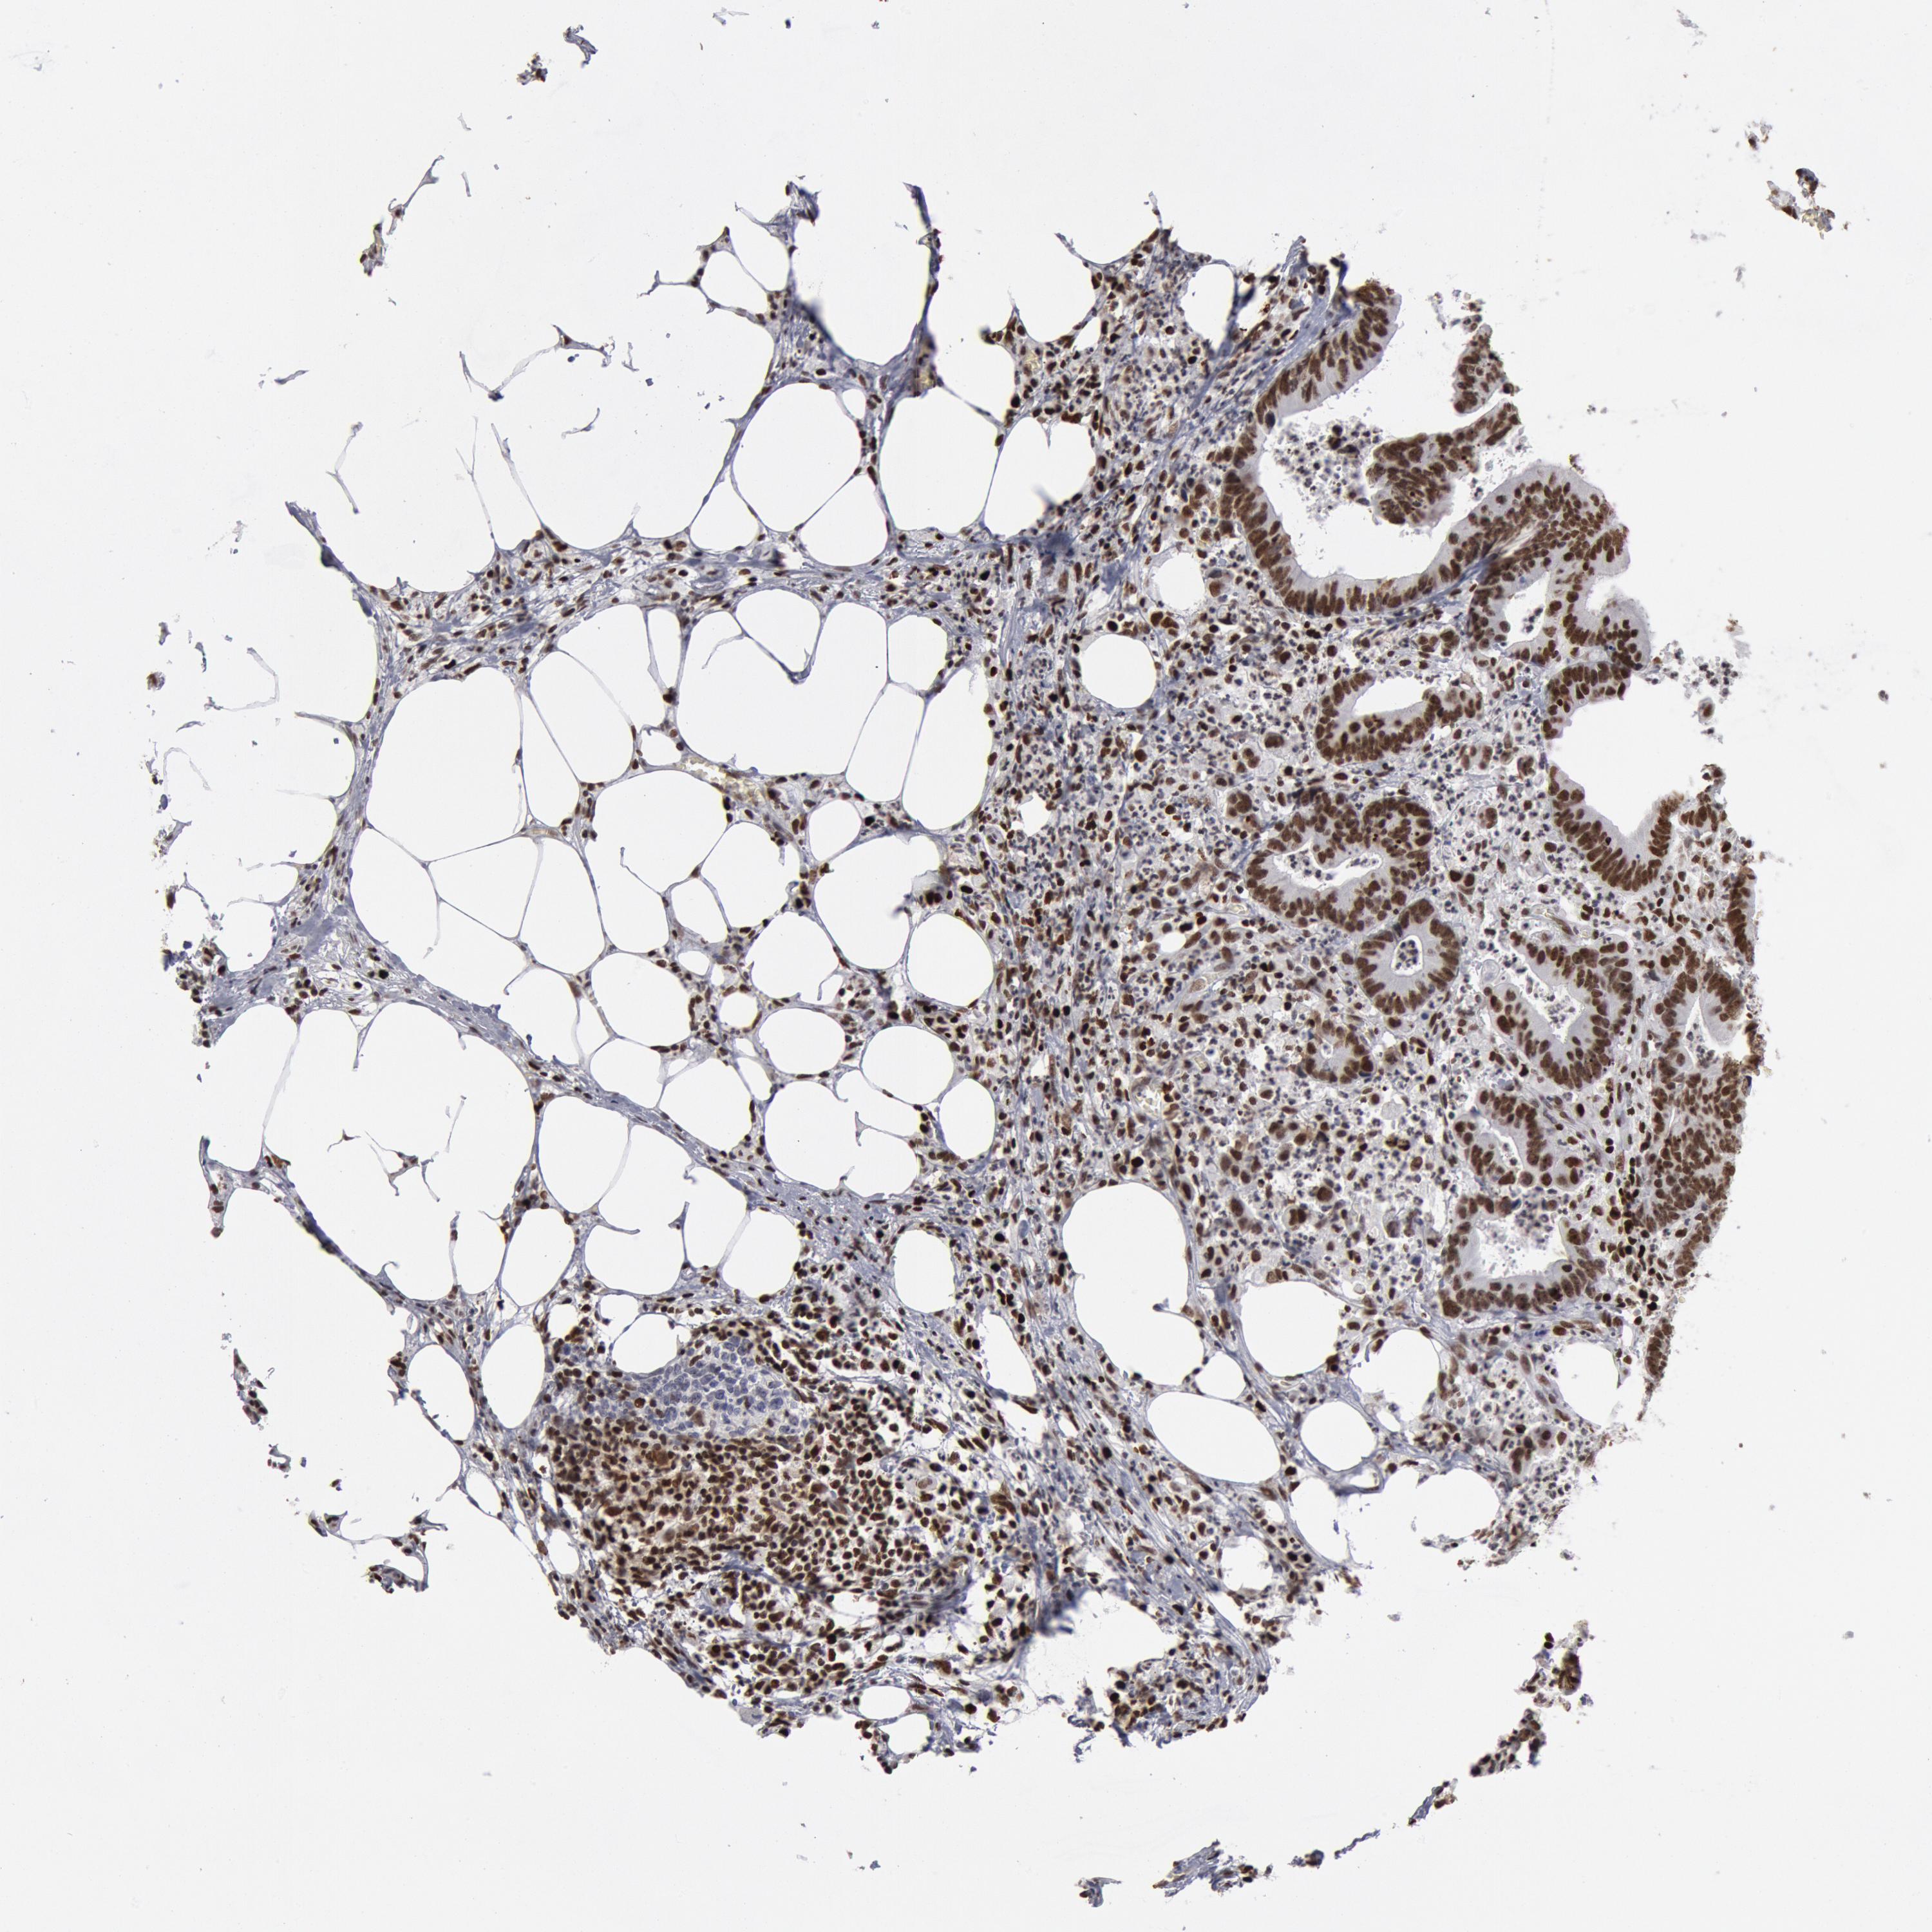

CANCER COLORECTAL CANCER Show tissue menu

Colorectal cancer

Human cancer

Colon adenocarcinoma